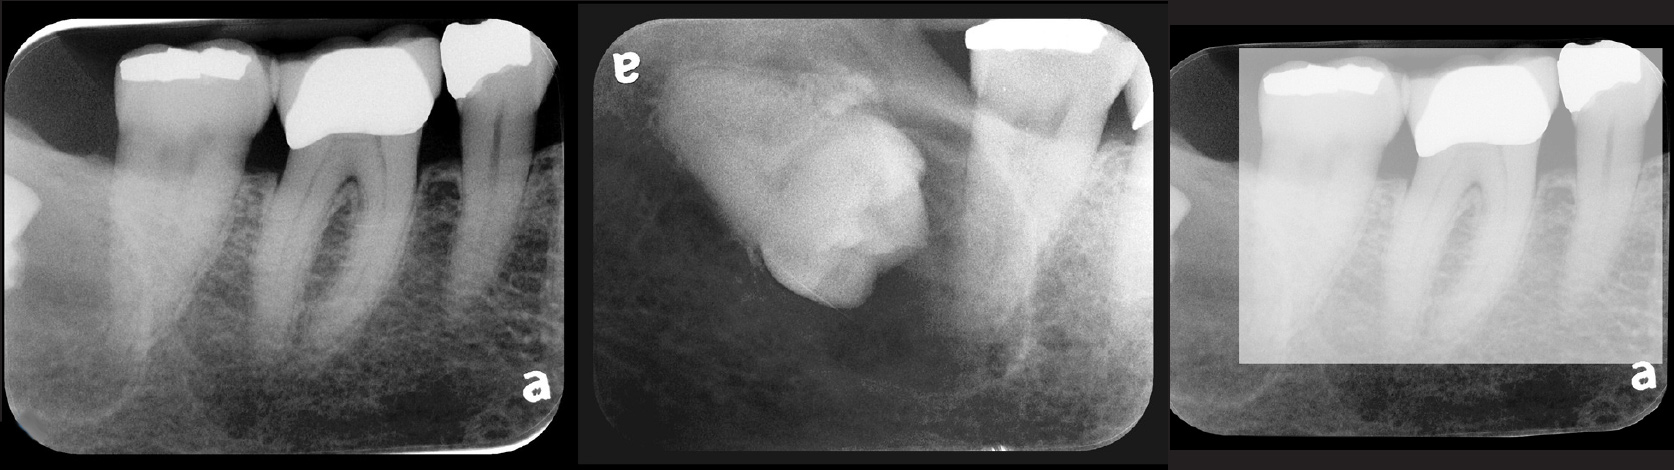

Fig 4. Severe dilaceration of root of tooth No. 17 and

curvature of roots of No. 18. Mandibular canal and inferior border of mandible are

easily visualized. If extraction of No. 17 is planned, a 3D CBCT study is required

due to proximity of tooth root to vascular and inferior alveolar nerve contents of

mandibular canal and possibility of surgical complications.

Figure 4

Fig 5. Bilateral concerns for this patient are evident on these PSP

radiographs. Tooth No. 17 may exhibit pathology distal to the root. In

addition, extreme length of root of tooth No. 32 through the entire height

of the body of the mandible is cause for concern if extractions of Nos.

17 and 32 are planned. Three-dimensional CBCT study and alerts to

the patient as to the potential surgical complications on extractions are

required in this instance. There is no benefit to panoramic radiography

in this case.

Figure 5

Fig 6. PA radiograph showing 90-degree dilacerations of

mesial and distal roots of tooth No. 32 and intersection of mandibular

canal with these roots. Extraction of tooth No. 32 requires 3D study, and

patient was advised as to this necessity.

Figure 6